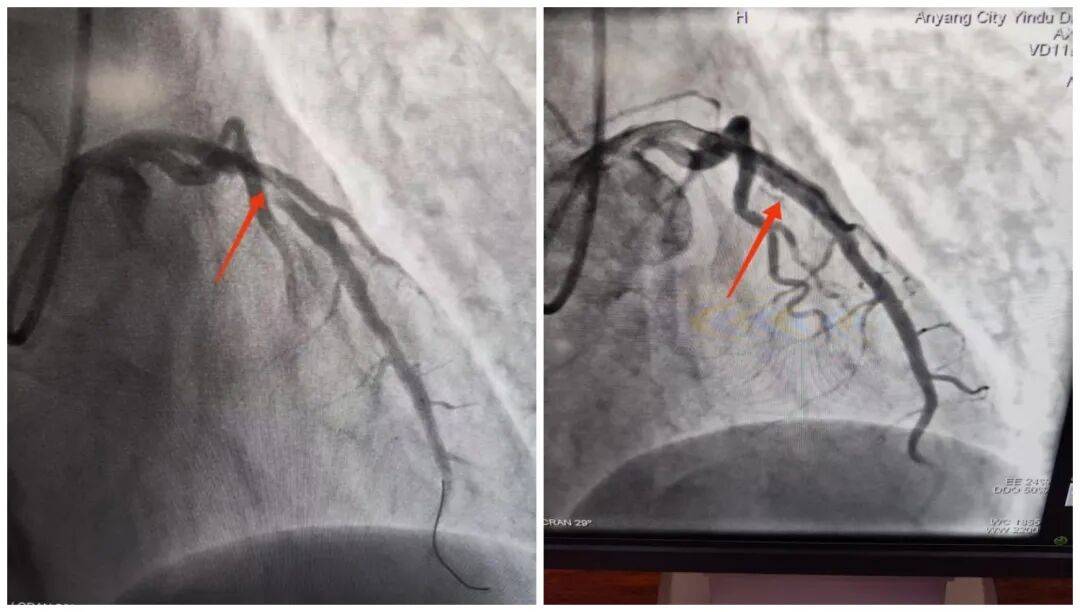

14:54,承载着生命希望的救护车抵达殷都区人民医院大门口。14:56,刘大爷被推至导管室门口,早已等候在此的医护团队立即上前,无缝衔接将刘大爷推进导管室,手术随即开始。15:18,医院介入团队精准操作,治疗导丝成功通过病变部位,血管开通的关键一步顺利完成。15:50,手术圆满结束,成功挽救了濒临坏死的心肌。从刘大爷到达殷都区人民医院门口到成功开通堵塞血管,整个过程仅用了24分钟,这一速度远优于国际通行的90分钟黄金标准。